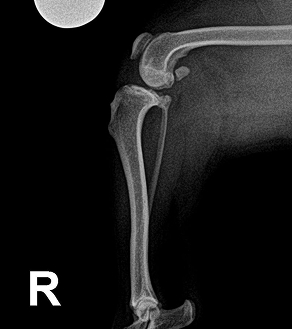

BEFORE

십자인대 파열의 경우, 부분 파열일 경우에는 안정적 관리와 운동 제한으로 회복을 도모할 수 있으나,

완전 파열이 확인된 경우에는 수술이 가장 효과적이고 근본적인 치료 방법입니다. 하지만 저희는 단순히 "무조건 수술"을 권하지 않습니다.